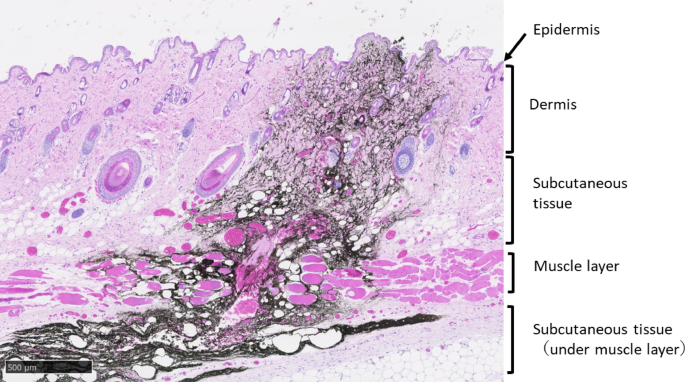

In this study, MTX, an autoimmune disease treatment drug, was used, and its usefulness in intradermal administration was evaluated. However, commercially available RA treatment drugs are subcutaneous injection preparations. Therefore, in this study, although using rats, we compared PK and BA across various administration methods (IV, PO, SC) to evaluate potential SC administration via the PJI. The results showed PK parameters and BA similar to those after SC administration, suggesting the potential of the PJI for SC administration in rats. To date, it has not been reported whether the PJI can administer drugs subcutaneously. Therefore, we first investigated the dispersion pattern of black ink via the PJI to determine where the ink reaches the skin and/or subcutis. To the best of our knowledge, this is the first report showing that black ink injected on the skin surface of rat flanks using the PJI is extensively and rapidly distributed in the subcutaneous tissue immediately after administration and reaches deep into the subcutis (Fig. 1). Therefore, this PJI administration method is thought to inject to the same skin depth as SC injection, that is, the drug can penetrate into subcutaneous tissue including the muscle layer. Second, we investigated the PK and BA of MTX in rats after four different administration methods: IV, PO, SC, and PJI. The PJI is in principle the same administration route as SC. In the comparison between PO and parenteral administration (IV, SC), the PK results in this study were similar to those in previous studies, showing that parenterally administered MTX led to more rapid, complete absorption and higher serum levels than PO administration8,9,10. The comparison between PJI and SC administration showed that there were no statistically significant differences in the PK and BA of MTX (Table 1, Figs. 2 and 3). For each PK parameter, Cmax was slightly higher in the PJI than in the SC group, although the differences were not statistically significant. In addition, the plasma concentration of MTX (mean ± SD) at 0.17 h in the PJI group (1.49 ± 0.04 µg/mL) was significantly higher than that in the SC group (0.77 ± 0.18 µg/mL, p < 0.05). These differences in Cmax at 0.17 h were likely due to differences in injection power, as the PJI injects the agent using the power of the gas explosion gas generator. MRT0–∞ with the PJI was slightly shorter than that with SC administration, although not a statistically significant difference. This might be due to a larger drug absorption rate constant (ka) because the PJI uses the power of the gas explosion to inject MTX.

The relative BA after PJI compared with SC administration was 101.7%. Notably, the AUC0–∞ and absolute BA after PJI and SC had nearly the same values as after IV administration. In addition, although not a statistically significant difference, absolute BA with the PJI tends to be slightly greater than with SC administration, which may be due in part to MTX absorption from the skin with the PJI via the muscle layer under subcutaneous tissue. Therefore, this is the first report that a low-molecular-weight molecule such as MTX demonstrated rapid distribution over a wide SC tissue area including the muscle layer under that tissue after the PJI was injected into rat flank skin surface, with the same BA as after SC injection.

This study had several limitations in considering the application of this PJI method to humans. First, we investigated the diffusion pattern and penetration depth of black ink in the skin and/or subcutaneous tissue of rats via the PJI (Fig. 1) in this study. The results showed that administration via the PJI may reach depths beyond the SC layer of rats. These results suggest that a portion of the MTX dose may be administered intramuscularly in rats, and that PK parameters may change compared with SC administration. However, as shown in Figs. 2 and 3 and Table 1, the PK parameters obtained with PJI administration were similar to those obtained with SC administration, suggesting that the MTX administration method using the PJI is essentially equivalent to SC administration. It should be noted that the results in this study were obtained in rats using a PJI device designed for rats (Actranza® lab.). Because human and rat skin differ significantly in thickness and texture, it is unclear whether the results of this study can be extrapolated to SC administration in humans. Therefore, we consider that pig or human skin, which are more commonly used as nonclinical trial models for transdermal administration due to their similarity in skin thickness and texture, or clinical trials in humans, are necessary to ultimately verify the potential of MTX SC administration using a PJI device designed for humans. Second, it was a fixed-dose animal study, and the MTX dose used was very high at 2.5 mg/kg, compared with the usual dose of MTX for the treatment of RA in humans (i.e., 7.5–15 mg once weekly)17,29. The possibility that high MTX dosage may mask differences between administration methods was not examined. In the future, it will be necessary to examine differences in BA between the PJI and other administration methods using several MTX dosages that take clinical dosages into consideration. Third, this was only a pharmacokinetic study to examine BA, not a bioequivalence (BE) animal study. Since it was difficult to conduct a BE study in rats, we evaluated BA using a parallel-group design in this study. Given the small sample size of 3–4 rats used in this study, there is a possibility that the power was insufficient. When interpreting the results of this study, this point should be noted. Further studies with larger sample sizes or BE studies using crossover trial designs in other animal species, such as pigs or humans, are necessary. Fourth, we do not have the safety data on the potential damage of local tissue after high-pressure injection via the PJI. However, it was reported that in a rat model to evaluate the usefulness of the PJI as a DNA vaccine tool, histopathological analysis of skin damage caused by the PJI was performed at 0, 6, and 24 h after Luc-plasmid DNA injection, showing that PJI administration caused small spherical cleavages and swelling that were observable up to 6 h postinjection. Those small spherical cleavages and swelling disappeared by 24 h. No other remarkable intradermal inflammation or bleeding was observed at any observation time point. Furthermore, no remarkable adverse events were observed at 24 h after PJI administration. These results show that the PJI did not induce skin damage complications after plasmid DNA injection or bleeding at the injection site30. In another clinical study19, the PJI was also reported to be safe in a human. The data mentioned above did not include safety data on PJI preparations of MTX in human RA patients Therefore, we need to pay attention to the safety of PJI preparations with MTX in human RA patients, due to interspecies differences. Accordingly, further BE studies in humans are needed to demonstrate BE, including safety, between PJI and SC administration using the METJECT subcutaneous syringe/pen. Fifth, the effects of drug formulation characteristics (drug concentration, volume, excipients, etc.) on PJI performance were not examined in this study. In the case of drug solutions that are suspensions, particle size and viscosity may affect injection behavior. However, the MTX solution used in this study was a nonviscous aqueous solution, and the drug volume administered was 50 µL, which is the standard container unit volume. Therefore, it was considered unlikely to affect the performance of the PJI. Consequently, the MTX solution used in this study can be administered via the PJI without issues, similar to existing clinical formulations, and concerns regarding performance degradation due to drug concentration or additives were limited in this study. However, in the future, if high-concentration drug solutions, large volumes, or viscous additives (excipients) such as absorption enhancers are used, it will be necessary to evaluate the potential impact of these drug formulations on PJI performance. Sixth, since PJI devices are not currently commercially available, it is not possible at this time to compare their cost to that of existing MTX injections. However, this device can be used repeatedly, and consumables are limited to drug-filled container units. Therefore, initial costs are concentrated on the purchase cost of the device itself, and subsequent costs depend solely on the drug container units. If appropriate pricing is established for the drug container units, it is expected that cost–benefit comparable to or exceeding that of existing injectable formulations can be achieved. Additionally, previous studies reported that patients demonstrate greater willingness to pay for administration methods that offer reduced pain associated with injection, improved operability, enhanced drug efficacy, and improved side effect profiles27. Finally, this study was an animal experiment using rats, and at present, no data on fear responses associated with sound or pressure stimuli and ease of use for patients have been obtained. These data need to be collected as future research topics. Although the use and operability of this product may require a certain amount of skill and practice, the injection button is flexible and can be pressed without excessive force. It can be used simply by replacing the disposable container unit (cartridge) filled with the drug solution, and attachment and removal are relatively easy. However, depending on the degree of joint dysfunction in RA patients, it may be difficult to operate the PJI or replace the container unit. Therefore, it is essential to evaluate the operability based on the degree of joint dysfunction in RA patients. In addition, prior education and training are required to ensure proper use. These measures are expected to increase the feasibility of administration by RA patients and caregivers by reducing patient anxiety and pain and avoiding the risk of needle-stick injuries and drug exposure for caregivers. Therefore, the PJI is suggested to have greater clinical utility than conventional formulations. Overall, SC administration using the PJI is expected to contribute to improved tolerability, medication adherence, and treatment continuity. Furthermore, enabling self-administration at home may also contribute to improved treatment outcomes and patient satisfaction with quality of life (QOL). However, currently, there are no data available for humans, particularly RA patients. Going forward, it will be necessary to collect such data through clinical trials during the clinical development process and utilize it to improve the PJI device.